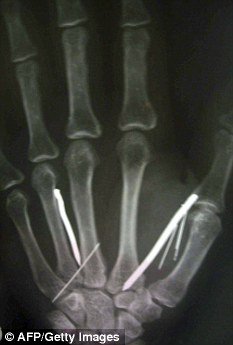

X光下显示艾里雅瓦蒂手臂上的数根铁钉 国际在线发

艾里雅瓦蒂手掌里也被狠心的雇主钉入了钉子 国际在线发

现年49岁的斯里兰卡女佣名叫阿立亚瓦提(L.G. Ariyawathi),21日从沙特回国后,感觉身体剧痛,于是住院治疗。她说,她的雇主把钉子与针烧红,再插入她体内。X光透视显示,她体内有24根钉子与针。

这些钉子长度从2.5到5厘米不等,针约2.5厘米长。医生从她的腿部与额头等部位拔下了这些钉子与针。

医生说,还有6根针在瓦立亚瓦提手上,但是无法取出,因为手术可能会破坏她的神经与动脉。但是这些针对她的健康没有伤害。